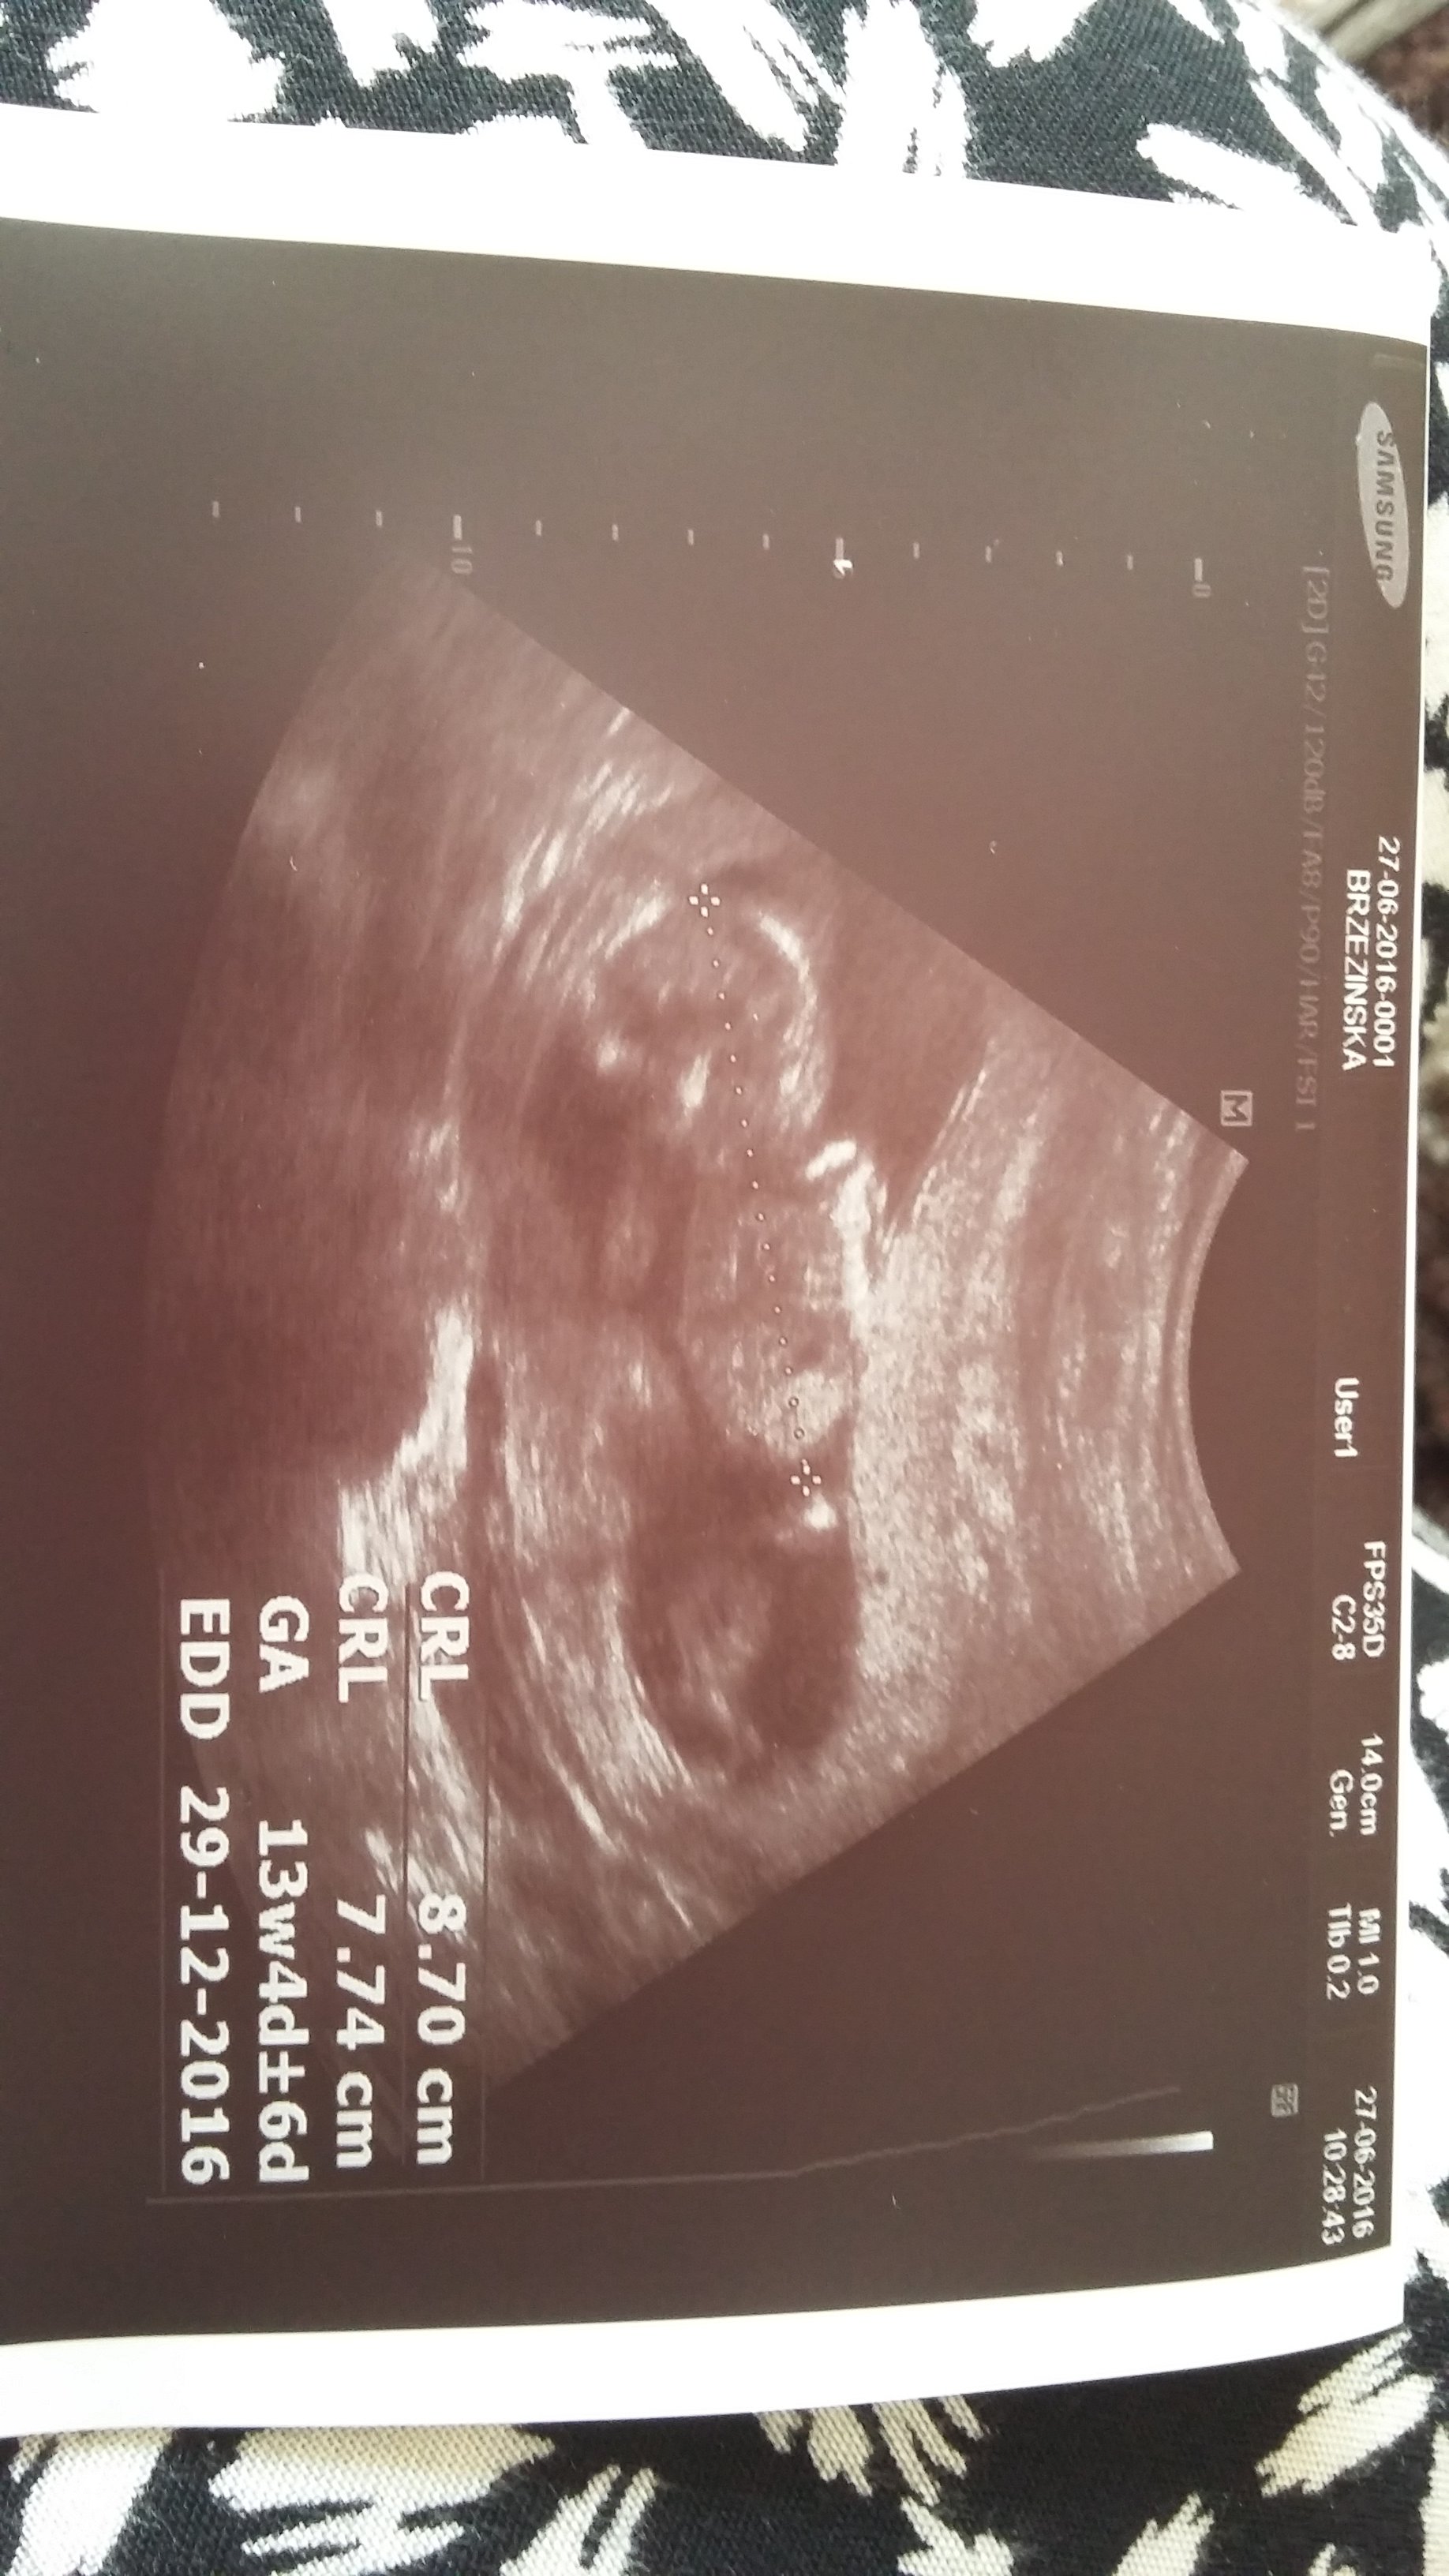

Mój bobas ma już 8,7 cm :) dziś był leniwy strasznie :) nie wiadomo co bd dopiero jak urodze się dowiem :P tak dr powiedział. Ale jest za wcześnie jeszcze żeby poznać płeć.

Wynikami mam się nie przejmowac

Leki juz odstawiamy wiec tylko femibion mam brać :)